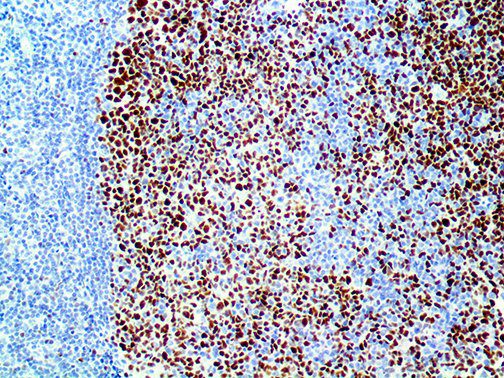

The first cytokines released are interleukin 1β (IL-1β) and tumor necrosis factor-α (TNF-α), which attract a variety of circulating white blood cells (WBCs) to the infection site, including neutrophils, monocytes, macrophages, and natural killer (NK) cells. This response, along with the antipathogenic chemicals released by these cells (i.e., complement), comprise the innate immune response. These cells directly attack the invading pathogen and also release additional cytokines, chief among them interleukin-1 and 6 (IL-6). IL-6 is essential for invoking the adaptive immune response, which calls T-cells, B-cells, and T helper (Th) cells to the infection site. IL-6 also stimulates further recruitment, proliferation and activation of macrophages.

It is the ICU physician who is most likely to witness one of the deadliest manifestations of the abnormal immunological response, the cytokine storm syndrome (CSS). This response is also referred to by some as the cytokine release syndrome (CRS). CSS is characterized by continuous activation and expansion of macrophage and lymphocyte populations, which secrete large amounts of cytokines, causing the cytokine storm. This massive cytokine release is akin to hemophagocytic lymphohistiocytosis (HLH) disease, a syndrome characterized by initial unchecked and persistent activation of cytotoxic T lymphocytes and NK cells.

Clinical and laboratory manifestations of HLH include fever, enlarged liver and/or spleen, neurologic dysfunction, coagulopathy, liver dysfunction, cytopenias (i.e., low levels of erythrocytes, leukocytes, and/or platelets), hypertriglyceridemia, hyperferritinemia, hemophagocytosis, and eventually diminished NK cell activity as the immune system becomes progressively paralyzed. HLH can be familial (primary HLH) or secondary to another disease process (sHLH), such as rheumatic disease, in which it is referred to as macrophage activation syndrome (MAS, characterized by elevated ferritin).